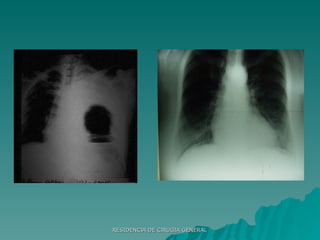

ETAPA HOSPITALARIA ABCDE LABORATORIO Hematocrito Glóbulos Blancos Amilasa Grupo Sanguíneo y Factor Rh Orina Sonda Nasogástrica Sonda Vesical Radiografías Básicas Rx columna cervical Rx Panorámica de Pelvis Rx de Tórax (Frente) Otras Rx (Abdomen)